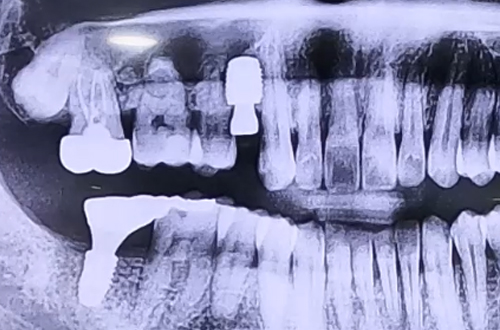

BEFORE

기존에 임플란트를 받던 치과가 문을 닫게 되어 치료가 중단된 것과 작은 어금니의 통증으로 내원해 주신 환자분이십니다.

본원에서는 다양한 종류의 임플란트를 취급하고 있기 때문에 어떤 임플란트를 사용했든 중단된 치료를 이어서 마무리할 수 있어 꼭 맞는 보철을 제작하여 마무리를 해 드렸습니다.

통증을 호소하신 어금니는 염증으로 인해 잇몸이 많이 약해져 있었으므로 발치 후 염증을 먼저 치료하는 기간을 가진 위 임플란트를 진행하는 지연 식립을 결정하였습니다.

잇몸이 충분히 단단해진 뒤 뼈이식과 함께 골유착에 용이한 임플란트를 선택하여 진행했어요.